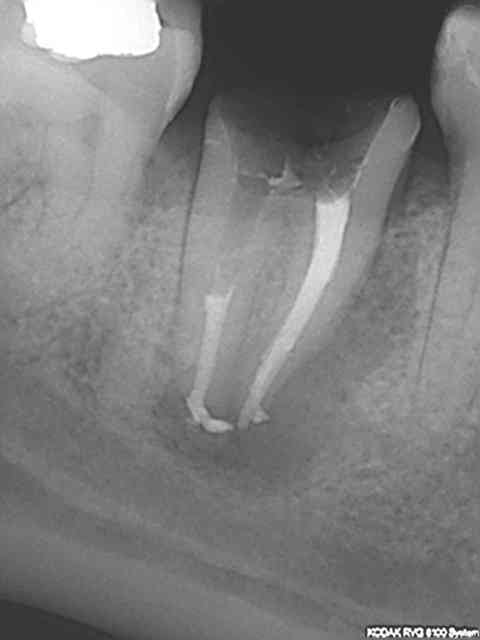

> @Chicot29: Tes endos sont superbes. Ce type de travail n'a aucune valeur pour

> santeclair et les autres guignols. Il n'y a que le prix, le prix, le prix. Tout

> le discours sur la qualité et le respect des normes de bonne pratique est de

> l'enfumage. Le but c'est de baisser le prix UN POINT C'EST TOUT. Il y a un

Ca c'était le cas de 14 h, voici le cas de 11h plus délicat. On verra ce que ca donne dans le temps ( finition au R40). C'est un peu creux en ce moment, heureusement qu'il y a des traitements réalisés conformément aux données acquises de la science à reprendre !)))))